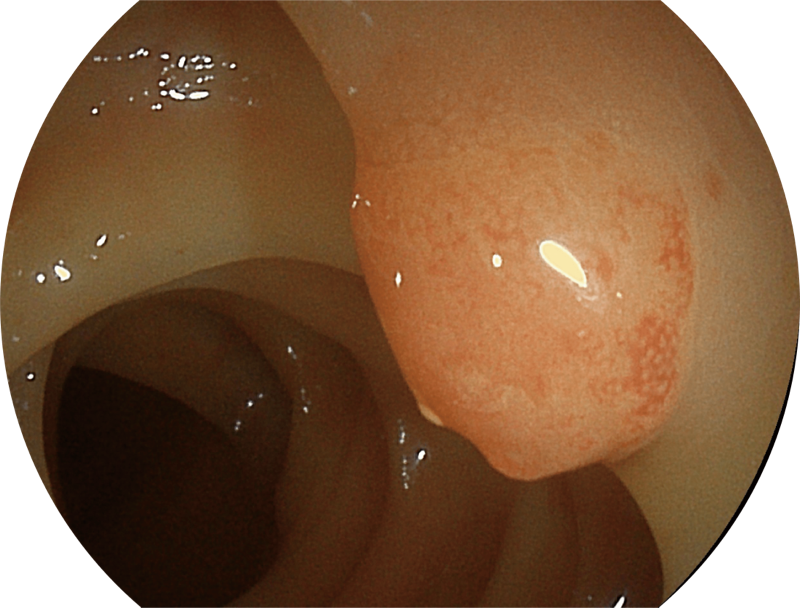

百万级像素高清传感器,1080P全高清视频信号输出,图像清晰。

能够凸显黏膜浅层和中层血管轮廓,适用于中、远景观察下的病灶识别和早癌筛查。

SFI图像